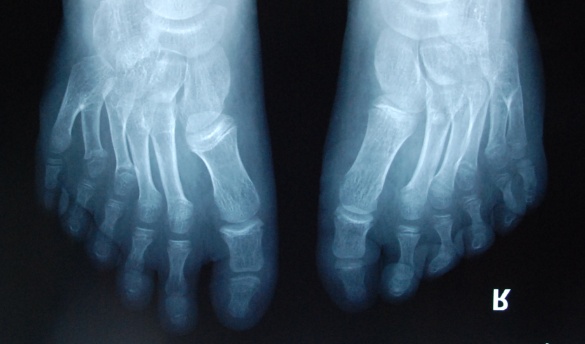

廈門眼科中心小兒眼科修陽(yáng)暉博士在日常的診療過(guò)程中就接診了不少這樣的的特殊家庭,讓其尤為印象深刻的就是一年前接診的BBS綜合征患者。當(dāng)時(shí)來(lái)院就診的是一對(duì)親兄弟,之前已在多家醫(yī)院做過(guò)檢查,因其均有較大散光和斜視,肉眼下眼底檢查未見(jiàn)異常,故外院均診斷為弱視,這也符合眼科門診常規(guī)的診斷邏輯與思維。但由于兄弟倆均有智力發(fā)育遲緩、特殊面容及四肢均有六指和六趾的特異體征引起了修陽(yáng)暉博士的警覺(jué):會(huì)不會(huì)是一種特殊遺傳性疾病或綜合征?后續(xù)的檢查結(jié)果進(jìn)一步證實(shí)了修陽(yáng)暉博士的懷疑---患兒均有夜盲,ERG、VEP及OCT檢查顯示雙眼的視網(wǎng)膜神經(jīng)上皮層結(jié)構(gòu)及功能均明顯異常。由于之前未遇到此種病例,修陽(yáng)暉博士在診斷一欄寫下視網(wǎng)膜色素變性并打上了個(gè)問(wèn)號(hào),同時(shí)留下了病人的聯(lián)系方式。

BBS綜合征(Bardet-Biedl綜合征)是一種主要累及纖毛結(jié)構(gòu)與功能的罕見(jiàn)常染色體隱性遺傳性疾病。纖毛分布于哺乳動(dòng)物體內(nèi)的大多數(shù)細(xì)胞,它是一種廣泛存在于各種細(xì)胞表面的細(xì)胞器,體型微小但結(jié)構(gòu)復(fù)雜、作用強(qiáng)大,能感知細(xì)胞外機(jī)械和化學(xué)信號(hào)變化并協(xié)助其轉(zhuǎn)導(dǎo)到細(xì)胞內(nèi)部從而引起細(xì)胞應(yīng)答。高等動(dòng)物的視覺(jué)、觸覺(jué)、嗅覺(jué)、聽(tīng)覺(jué)的傳遞都依賴于體內(nèi)外正常的纖毛結(jié)構(gòu)和功能。因此BBS綜合征常累及全身多個(gè)系統(tǒng)和器官,在臨床上主要表現(xiàn)為:視網(wǎng)膜色素變性、智力發(fā)育異常、向心性肥胖、多指(趾)、性腺發(fā)育異常、腎臟異常。除此之外還有許多諸如:語(yǔ)言發(fā)育障礙、聽(tīng)力異常、嗅覺(jué)異常、斜視、白內(nèi)障、散光、牙齒發(fā)育異常、短指(趾)、并指(趾)、肝纖維化、糖尿病、高血壓等表現(xiàn)。